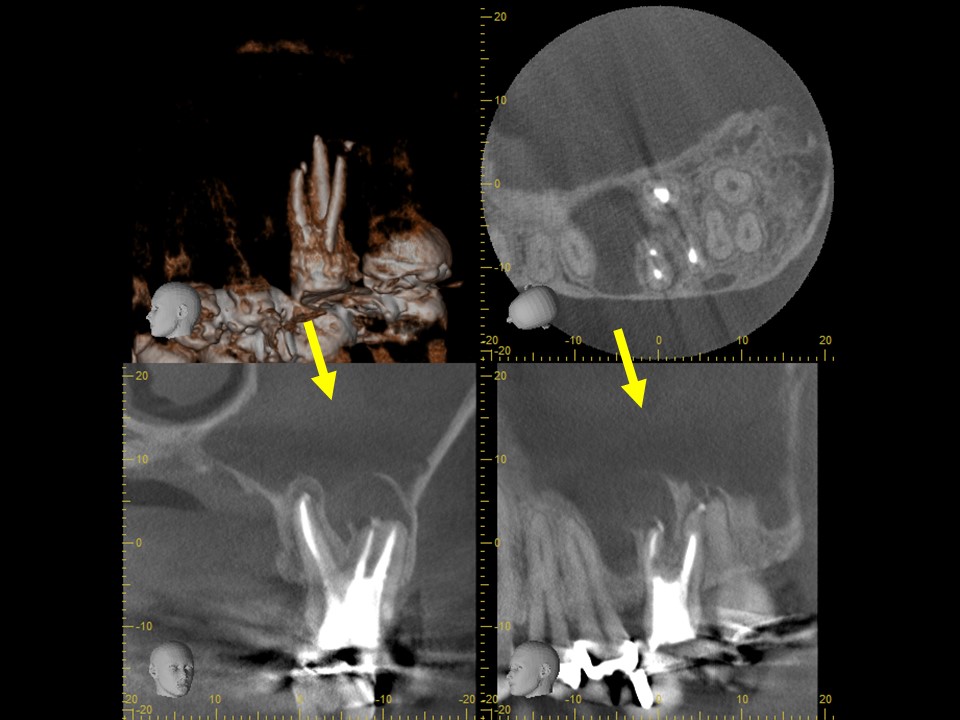

初診時CT。根管治療を何度も繰り返し行ったことで、歯根は無駄に削られて歯質が薄くなり、歯根の先端には穿孔(パーフォレーション)を生じていた。根尖病巣は認めない。